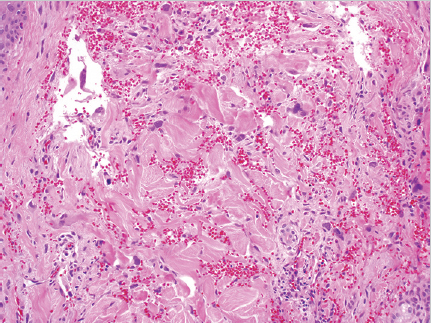

Fig. 5.9). Blood-filled channels or clefts are sometimes present with hemorrhage and necrosis.52 Lesions range from well to poorly differentiated. On histology, the lesion may be difficult to distinguish from other vascular and epithelial tumors including spindle cell carcinoma, malignant melanoma, and AFX; therefore, immunohistochemistry, and in particular vascular markers, should be used.53 Cutaneous angiosarcoma often stains positive for CD31 and Ets family transcription factor (ERG).54 Less sensitive stains include vascular endothelial growth factor receptor 3 (VEGFR-3), factor VIII, and D2–D40 monoclonal antibody.47,54 Angiosarcomas are usually negative for cytokeratin, S100, and desmin. Cutaneous angiosarcoma subtypes including the epithelioid subtype are diagnosed by histology and immunohistochemistry.